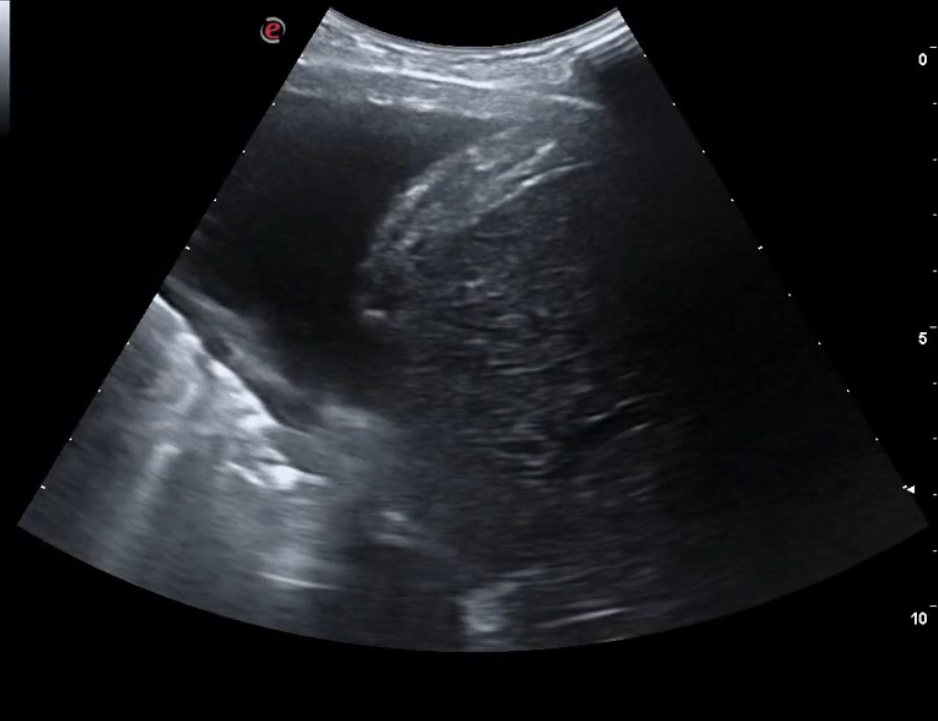

Para cuantificar el grado de insuficiencia cardíaca, además de la exploración cardiorrespiratoria y de miembros inferiores, la ecografía clínica pulmonar nos permitiría valorar, en los 18 campos, la presencia de líquido pleural, con la distorsión por aparición de mayor a tres líneas B, además de la valoración de líquido en senos costofrénicos.

Al iniciar el proceso, se recomienda la utilización de la ecografía pulmonar, además de extraer un péptido atrial natriurético y el Ca125; y la realización de un electrocardiograma para valorar sobrecarga vascular.

La ecografía pulmonar nos evita utilizar técnicas más invasivas y los ingresos tardíos hospitalarios para un control de la insuficiencia cardíaca, que se puede controlar en Atención Primaria utilizando el tratamiento adecuado precoz, y monitorizando la evolución con la ecografía.